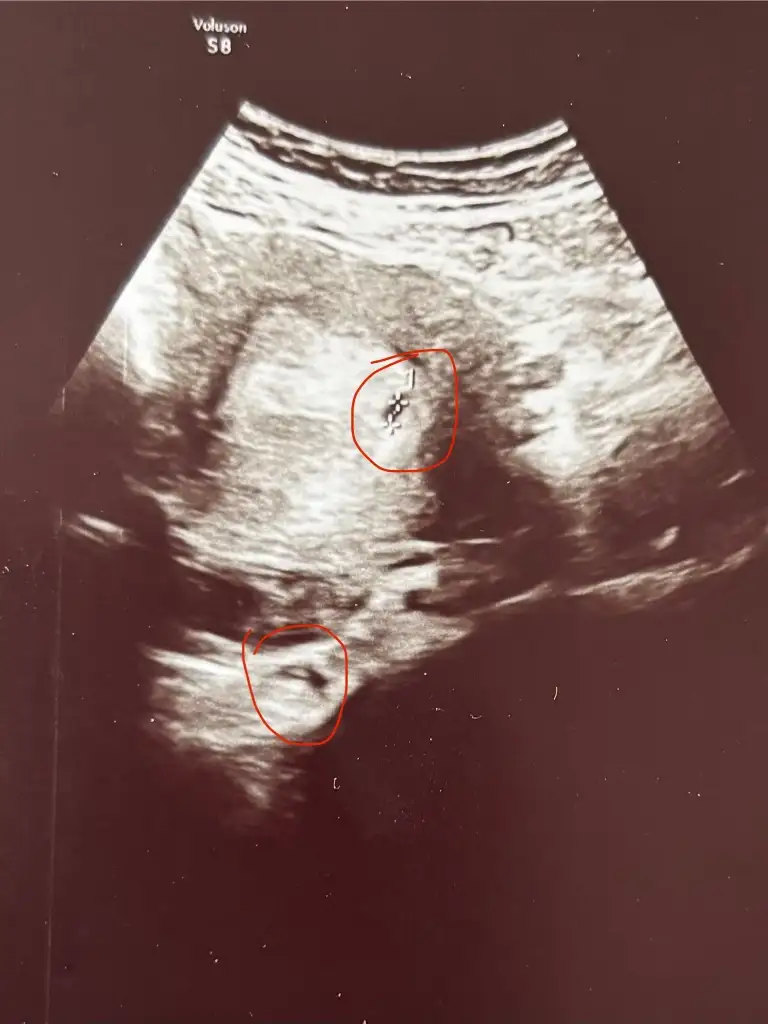

Bugün ilk ultrasonda 2 kese gördük doktor ikiz olma ihtimali var dedi ama beta sonucum da normal artıyor gibi ne dersiniz?

birmucizeistiyorum birmucizeistiyorum Sizin ilk ultrason görüntünüz var mı acaba? Biri yukarda ikincisi çok aşağıda gibi benim. Gördüğüm ikiz görüntülerinde keseler yan yana ya da daha yakınca alt alta oluyor sizinki nasıldı :oops: